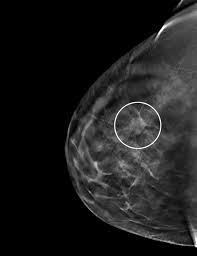

Screening mammograms have been used since the 1980s. The look of breast cancer on a mammogram a tumor or lump will appear as a focused white area on the mammogram. It can be any shape or size. Doctors in 147 specialties are here to answer your questions or offer you advice, prescriptions, and more. A radiologist will look at your mammogram. Breast cancer can present either as an area of focal asymmetry or when advanced can even present as a new asymmetry in breast size. Calcifications are calcium deposits within the breast tissue and they look like small white spots. It is also an anatomic test, which means cancer is detected based on changes in how the breast anatomy looks. It can be hard to know from a mammogram image whether the cluster is dcis or invasive breast cancer. The first is in my breast, and the second is in the lymph node in my armpit. You may notice dimpling or pitting, and the skin on your breast. (a cluster of microcalcifications can also be a benign finding on a mammogram. Larger deposits of calcium salts are called macrocalcifications.

On a mammogram, dcis usually looks like a cluster of microcalcifications.

A mammogram image has a black background and shows the breast in variations of gray and white. You may notice dimpling or pitting, and the skin on your breast. The rate of breast cancers discovered as dcis is thought to be increasing, but this is partially a testament to the effectiveness of mammographic breast cancer screening programs.ductal carcinoma in situ represents up to 30% of all new cases of breast cancer discovered by breast cancer screening. The first is in my breast, and the second is in the lymph node in my armpit. What does breast cancer look like on a mammogram? On a mammogram, dcis usually looks like a cluster of microcalcifications. It often feels hard, like a lemon seed, and usually immovable. The harmless nature of ultrasound machines also make them a benefit to patients. Generally speaking, the denser the tissue, the whiter it appears. This can help show if any findings are new, or if they were already there on previous mammograms. Dulce corazon the transfer of estrogen from a mother to her newborn child may cause breast lesions on the child. Microcalcifications on a mammogram may be indicative of breast cancer, but they are often benign. That makes it easy to detect abnormalities, which generally show up as white.